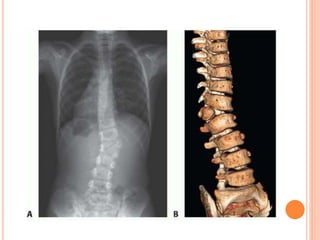

Anormalidades en el

raquis (hemivértebra).

Trastorno caracterizado por el fallo

congénito de una vértebra para

desarrollarse completamente.

Causado posiblemente por el

fracaso completo del núcleo

condral de un cuerpo vertebral.